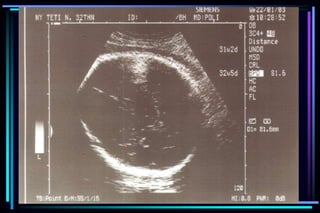

Evaluation of ultrasoundto determine gestational age  Crown Rump Length (CRL)  Biparietal diameter (BPD)  Femur Length (FL)  Head Circumference (HC)  Abdominal Circumference (AC)

Accuracy of ultrasoundmeasurement for different gestational groups Ultrasound parameter Accuracy  Gestational sac diameter + 7 days  Crown Rump Length + 3-5 days  BPD second trimester + 1 to 1.5 weeks  BPD third trimester + 2 to 4 weeks  FL second trimester + 1 to 1.5 weeks  FL third trimester + 3 to 3.5 weeks  Multiple parameter (2nd trimester) + 1.5 weeks  Multiple parameter (3rd trimester) + 2.5 weeks